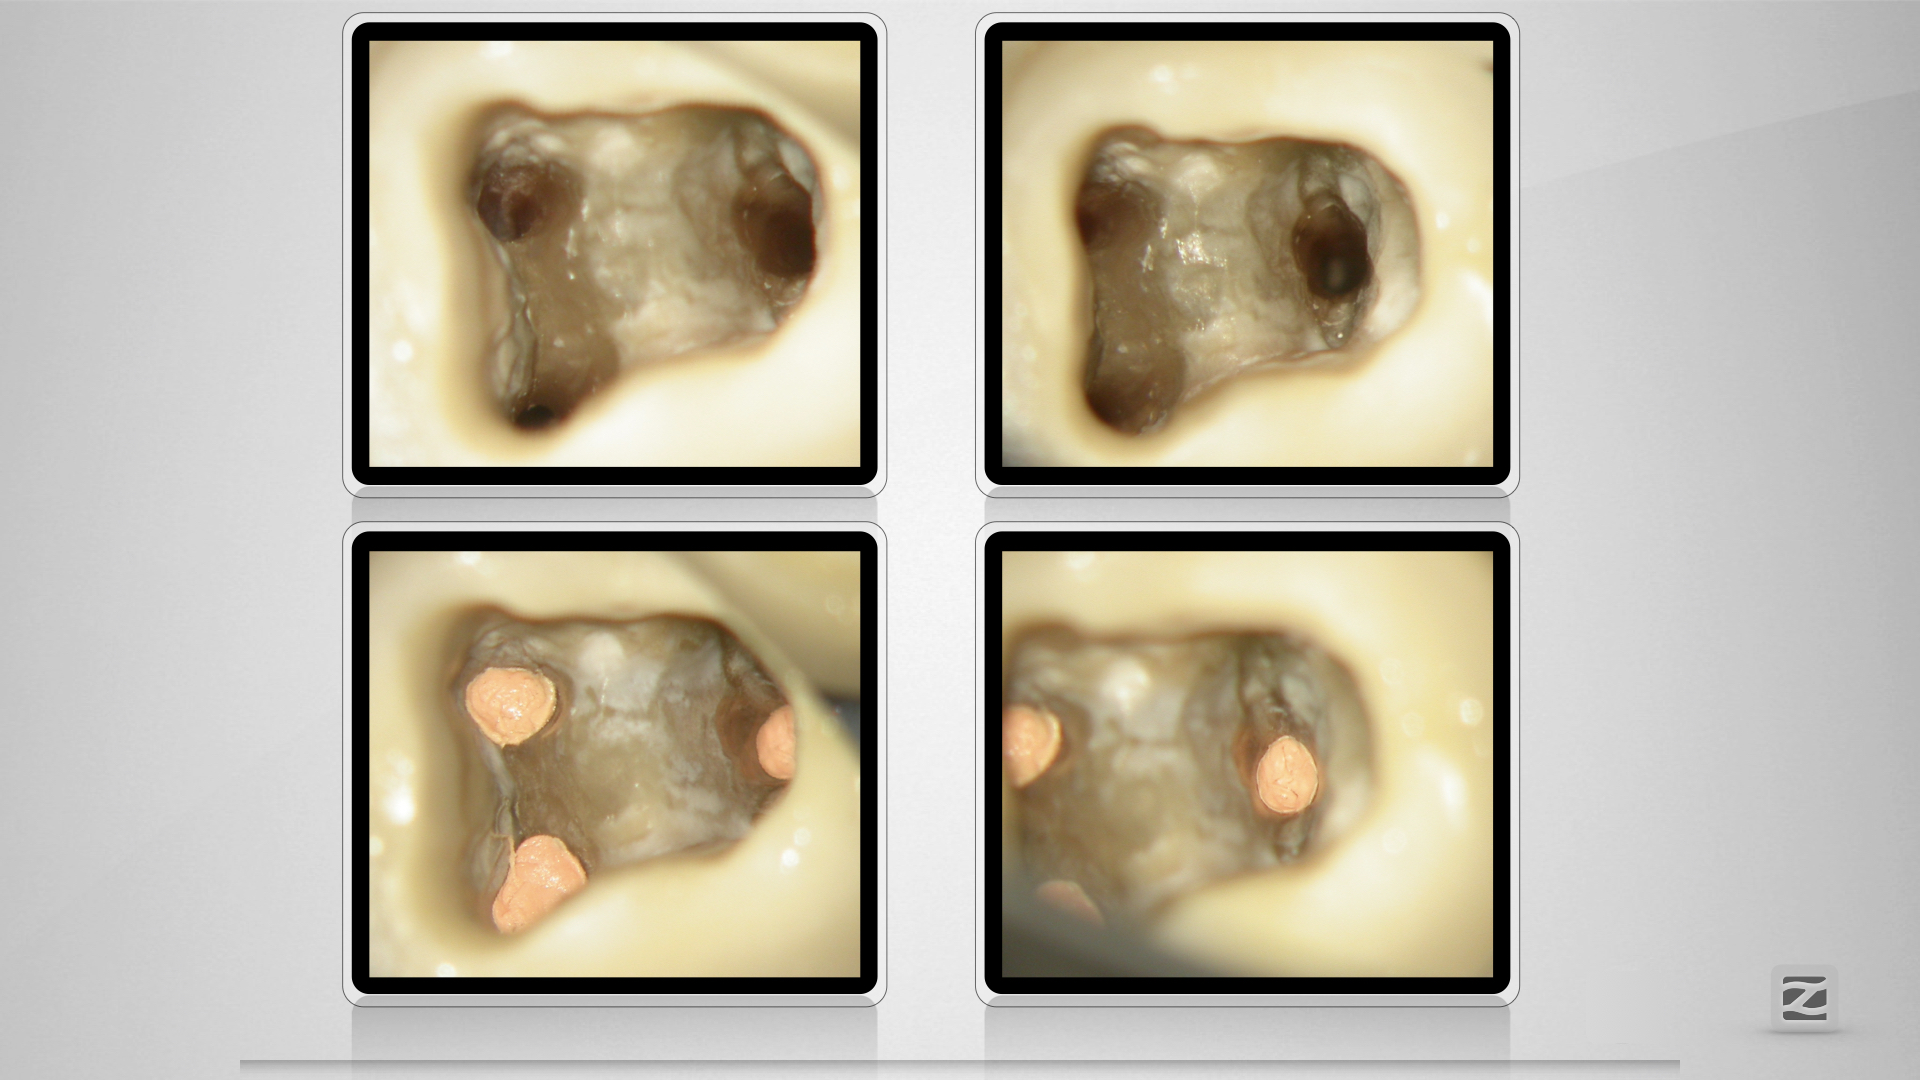

47D.009

Kuhfuß